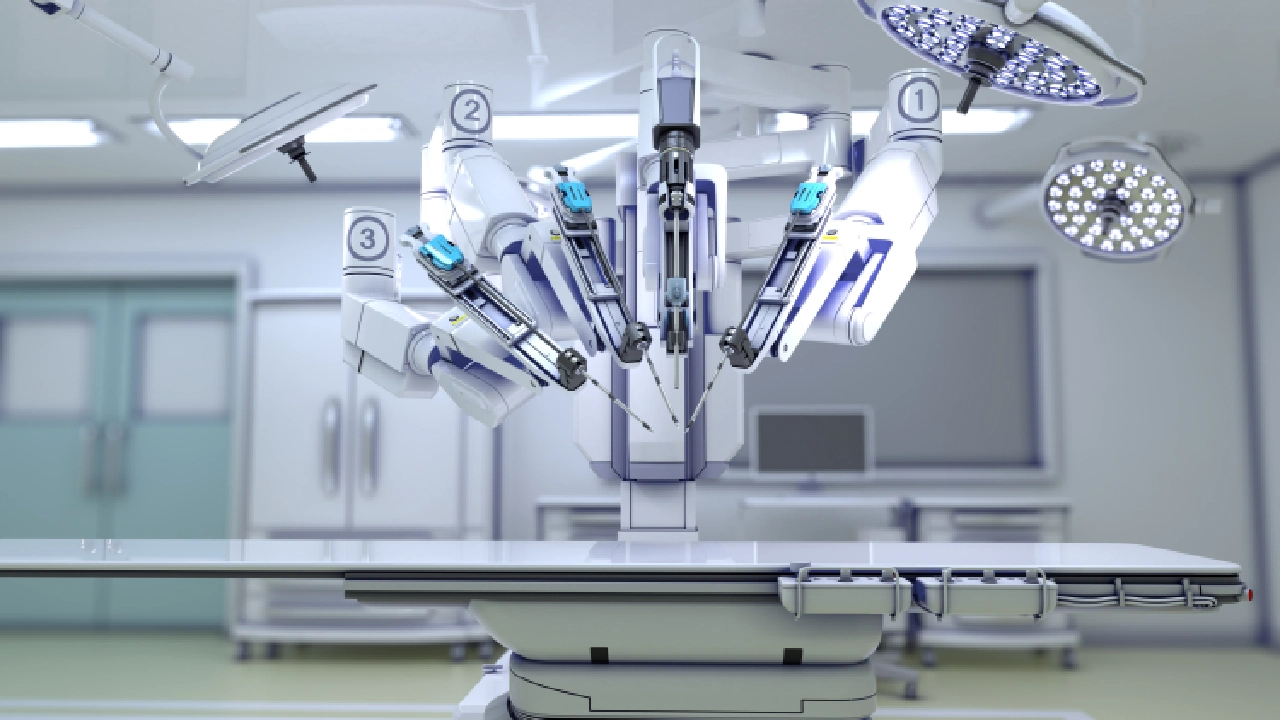

The Robotic Advantage in Pune Why settle for traditional methods when you can have sub-millimeter precision?

Dr. Gagare specializes in Robotic-Assisted Joint Replacement, a revolutionary approach that uses AI-driven 3D mapping to tailor surgery to your unique anatomy. For patients in Pune, this means a “natural-feeling” joint, significantly reduced post-operative pain, and a faster return to daily routines.

Unlike conventional surgery, robotics allows for better ligament balancing and bone preservation, ensuring your implant lasts for decades.